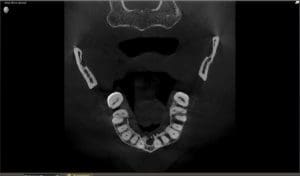

Dental Technology – Cone Beam CT Scan

Dental CBCT allows the dentist the opportunity to see the anatomy of the head and neck region in a three dimensional perspective. The distinct advantage of this is being able to detect dental infections or abscesses, which appear as radiolucencies (dark holes) around the roots of a tooth at an earlier stage than the traditional periapical radiographs would show. These abscesses are apparent on traditional dental radiographs only after the abscess has broken through the hard outer cortical plate of bone. When reviewing a CBCT, an abscess can be detected while it is still within the inner cancelous bone of the jaw. If the abscess can be detected earlier on a CBCT, before it has had an opportunity to destroy much of the surrounding bone, the infection can be treated before it has an opportunity to cause further destruction.

In our office we have found it interesting to compare a traditional dental radiograph to the CBCT and note the differences. It is astonishing that dental infections can often go undetected on the traditional radiographs. This is because there has to be about 40% loss of structure before it will begin to appear on a traditional radiograph. That is, almost half of the anatomy of the surrounding bone has to be destroyed by the infection before it can be detected on a traditional dental radiograph.